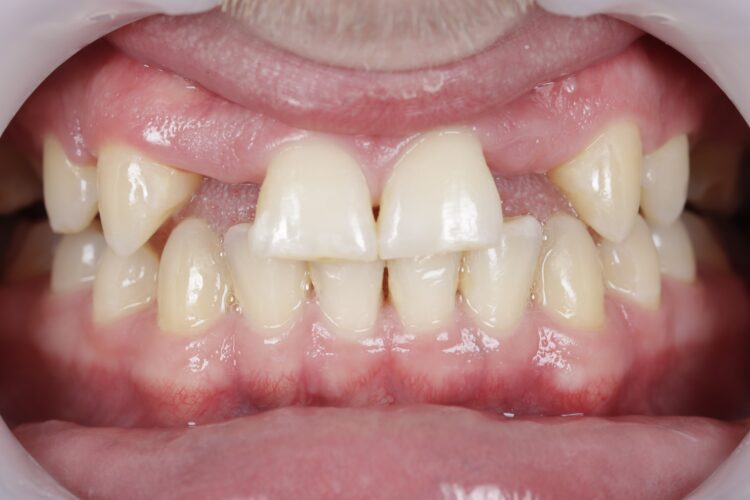

A young male presented with hypodontia and a number of missing permanent teeth. He was relatively unconcerned about his appearance and was driven more by his parents to seek treatment. As such, the patient was unsure about what he wanted from treatment and hesitant to undergo more than he absolutely needed to.

Clinical assessment

Upon assessment, it became clear that the patient’s tooth spacing was not ideal, and realignment would be necessary to create space for the lateral incisors. The patient had already been referred to me, and the option of no treatment had been discussed and ruled out. I presented the patient with two treatment options: Maryland Bridges or a combination of orthodontics and implant placement. The latter was my professional recommendation, and the patient provided informed consent to proceed, providing a clear understanding of his condition and the treatment options considered.